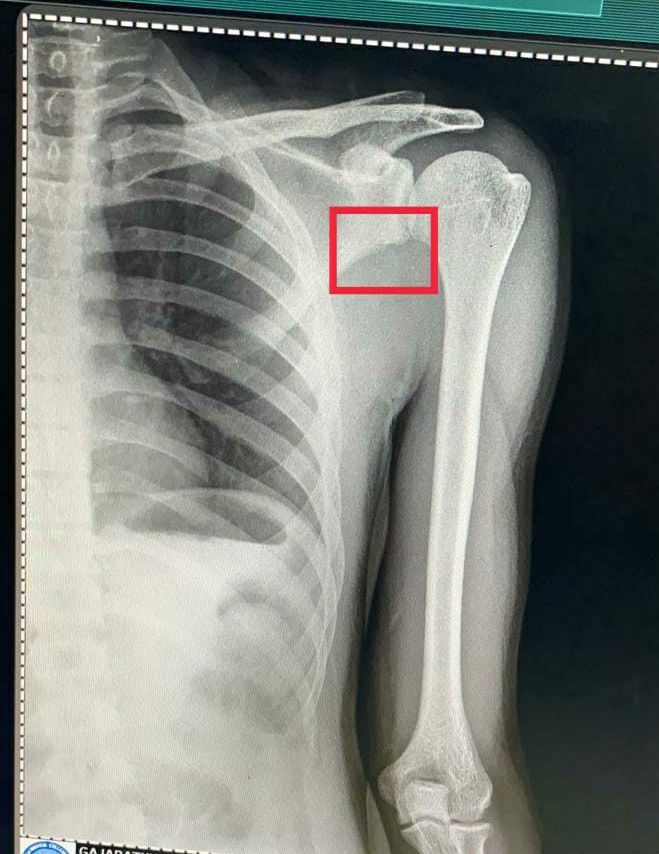

X ray chest PA view

What do u understand from this X ray? Comment ur diagnosis!

Recurrent anterior shoulder dislocation